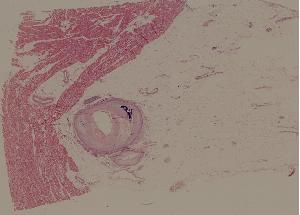

46.冠状动脉粥样硬化